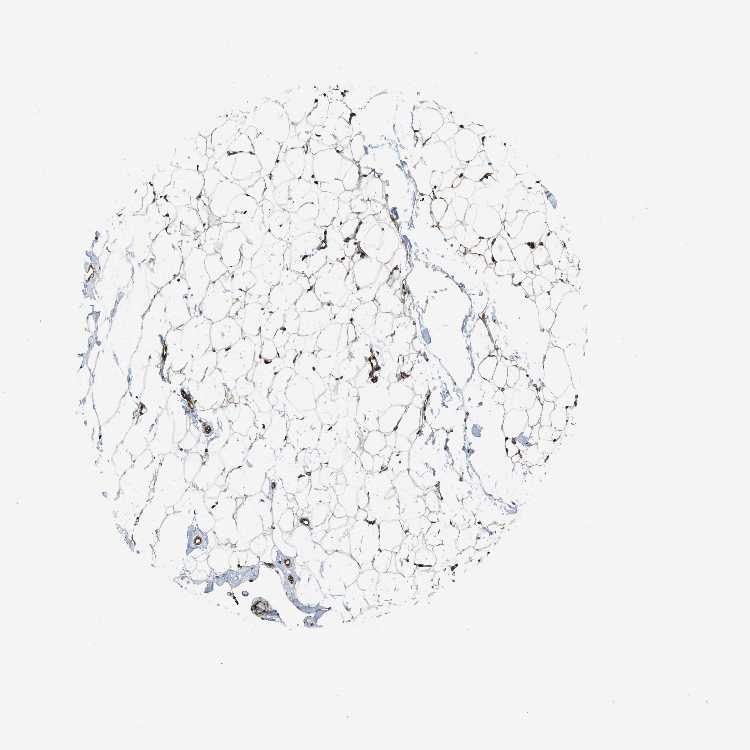

SOFT TISSUE 1 - Antibody stainingi

Antibody staining in the annotated cell types in the current human tissue is reported as not detected, low, medium, or high, based on conventional immunohistochemistry profiling in selected tissues. This score is based on the combination of the staining intensity and fraction of stained cells.

Each image is clickable and will lead to virtual microscopy that enables deeper exploration of all samples and also displays staining intensity scores, fraction scores and subcellular localization as well as patient and tissue information for each sample.

Antibody HPA008399Antibody HPA017017Antibody CAB015221

Fibroblasts LowNot detectedMedium

Peripheral nerve Not detectedNot detectedMedium